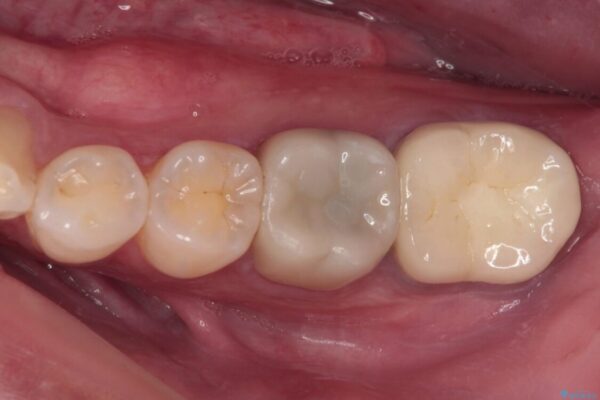

治療後

• 海外赴任前に治したい 割れてしまった奥歯のオールセラミッククラウン 治療後画像

治療後について

十分な土台の高さを確保できない状態であったので、維持力のある土台の形態に整えることで、極力長持ちする治療を心がけました。